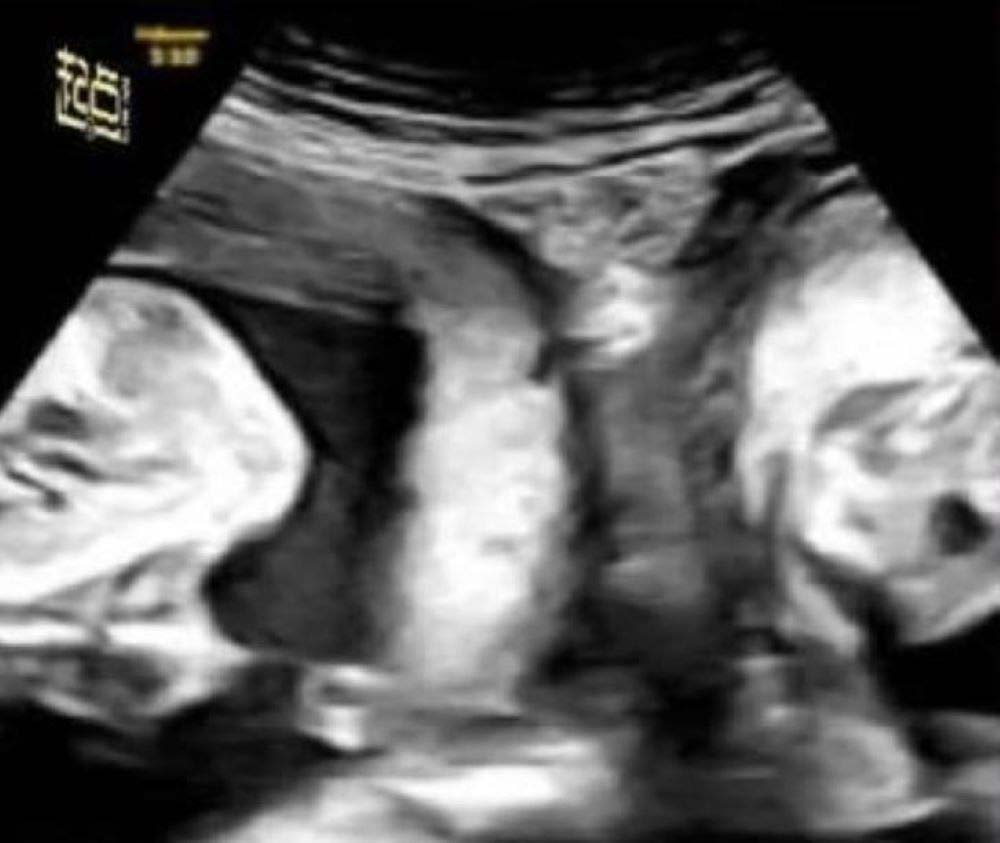

지난 9월 29일(현지시각) 베트남 매체인 베트남 익스프레스에는 중국 북서부의 리씨라는 여성이 지난 9월 초, 중국 산시성 시안4 병원에서 임신 8개월 반 만에 남자아이와 여자아이를 출산했다. 리씨는 선천적으로 자궁이 두 개인 ‘중복자궁’을 갖고 태어났다. 산시성 시안4 병원의 산부인과 전문의인 카이잉은 “중복자궁인 사람이 자연 임신을 통해 출산에 성공하는 것은 매우 드문 일이다”며 “이런 사건은 100만분의 1의 비율로 발생한다”고 말했다. 과거 리씨는 임신한 적이 있었지만 27주 만에 유산하게 됐다. 따라서 지난 1월 리씨가 다시 임신한 후, 산부인과 의사들은 건강한 출산을 위해 세심한 계획을 세웠다. 이 덕분에 제왕절개를 통해 건강한 상태의 3.3kg의 남자 아기와 2.4kg의 여자 아기 2명이 태어났다.

중복자궁은 자궁을 두 개 가지는 희귀한 신체 특징이다. 중복자궁은 특별한 증상이 없어 알아차리기 힘들다. 하지만 중복자궁을 가진 여성들은 대부분 과도한 월경량과 심한 월경통을 겪는 것으로 알려졌다. 중복자궁을 가진 여성은 자궁의 형태가 일반적이지 않아 조산이나 유산을 경험할 위험이 크다.